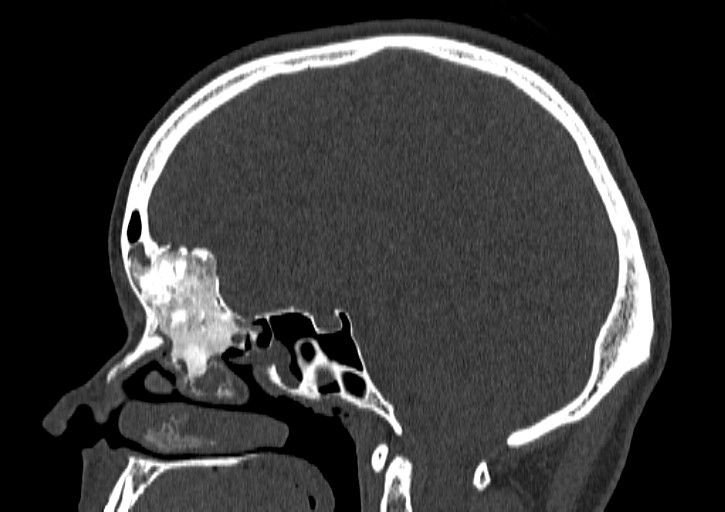

Zespół, w skład którego weszli prof. Paweł Słoniewski z Katedry i Kliniki Neurochirurgii oraz dr hab. Andrzej Skorek z Katedry i Kliniki Otolaryngologii mają na swoim koncie pierwsze sukcesy związane z leczeniem procesów patologicznych pogranicza nosowo-zatokowo-mózgowego. Interdyscyplinarność stanowi odpowiedź na rosnącą liczbę pacjentów dotkniętych schorzeniami rozwijającymi się na pograniczu dwóch powyższych specjalizacji. Owocem współpracy jest przede wszystkim podniesienie bezpieczeństwa zabiegu dla chorego. Dotychczas zoperowano 6 osób (2 z nowotworami złośliwymi i 4 z nowotworami niezłośliwymi), u których resekowano podstawę przedniego dołu czaszki (struktury kostne i oponę mózgową) wraz z guzem, a następnie odtworzono trwałą i szczelną barierę oddzielającą wnętrze czaszki od jamy nosa. W trakcie zabiegu korzystano z najnowocześniejszych urządzeń stanowiących wyposażenie sali operacyjnej Centrum Medycyny Inwazyjnej: neuronawigacji oraz z mikroskopu operacyjnego. Nie obserwowano istotnych powikłań leczenia.